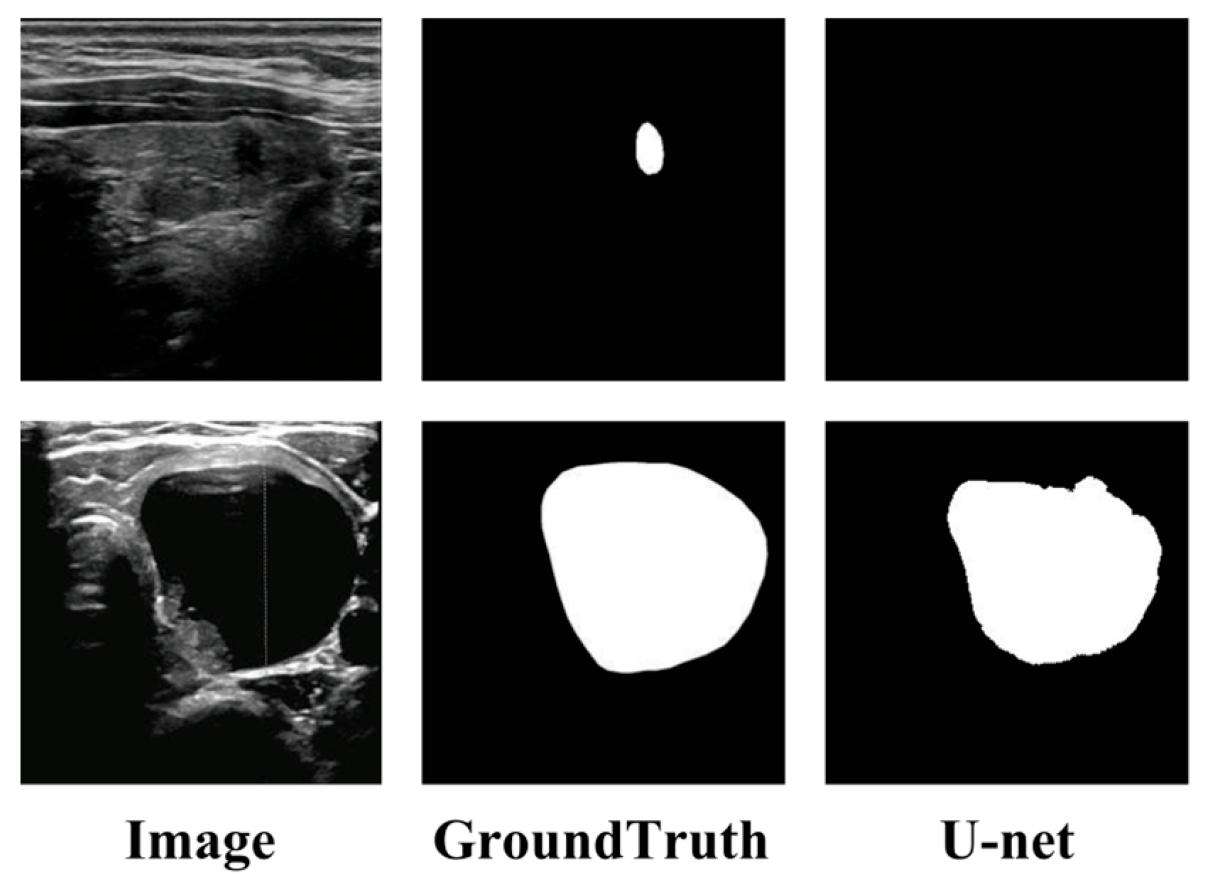

4.2. Comparison with the Other Methods